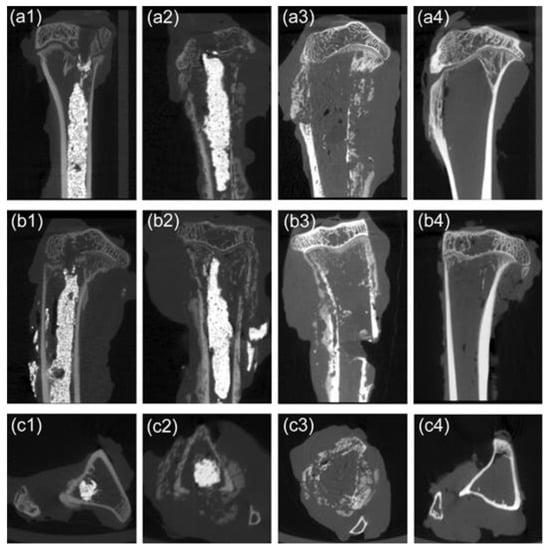

In addition, the incidence of pathologic fractures was 10% in the M-PMMA and control groups, which did not occur in the M-PMMA + AMF group. Furthermore, skeletal morphologies and bone resorption were evaluated by micro-CT after magnetic hyperthermia. Although the cortical bone thickness of tumor-bearing tibias in the M-PMMA + AMF group (Figure 6a1,b1,c1) was less than in the normal tibias (Figure 6a4,b4,c4), skeletal morphology still existed. However, the tumor-bearing proximal tibias in the M-PMMA (Figure 6a2,b2,c2) and control groups (Figure 6a3,b3,c3) were severely destroyed, the cortical bone was erosive, and the skeletal morphologies were almost destroyed. The bone volume of the tumor-bearing proximal tibias was measured by software (Figure 4d), and the results were tested with one-way ANOVA. The bone volume in the M-PMMA + AMF group was higher than in the other two groups (p < 0.05). Magnetic hyperthermia induced by PMMA-Zn0.3Fe2.7O4 bone cement can inhibit bone resorption.

Figure 6. Micro-CT image of the affected lower extremities in the different groups after magnetic hyperthermia. Sagittal section (a1), coronal section (b1), and cross section (c1) of the M-PMMA + AMF group. Sagittal section (a2), coronal section (b2), and cross-section (c2) of the M-PMMA group. Sagittal section (a3), coronal section (b3), and cross-section (c3) of the control group. Sagittal section (a4), coronal section (b4), and cross-section (c4) of normal tibias.